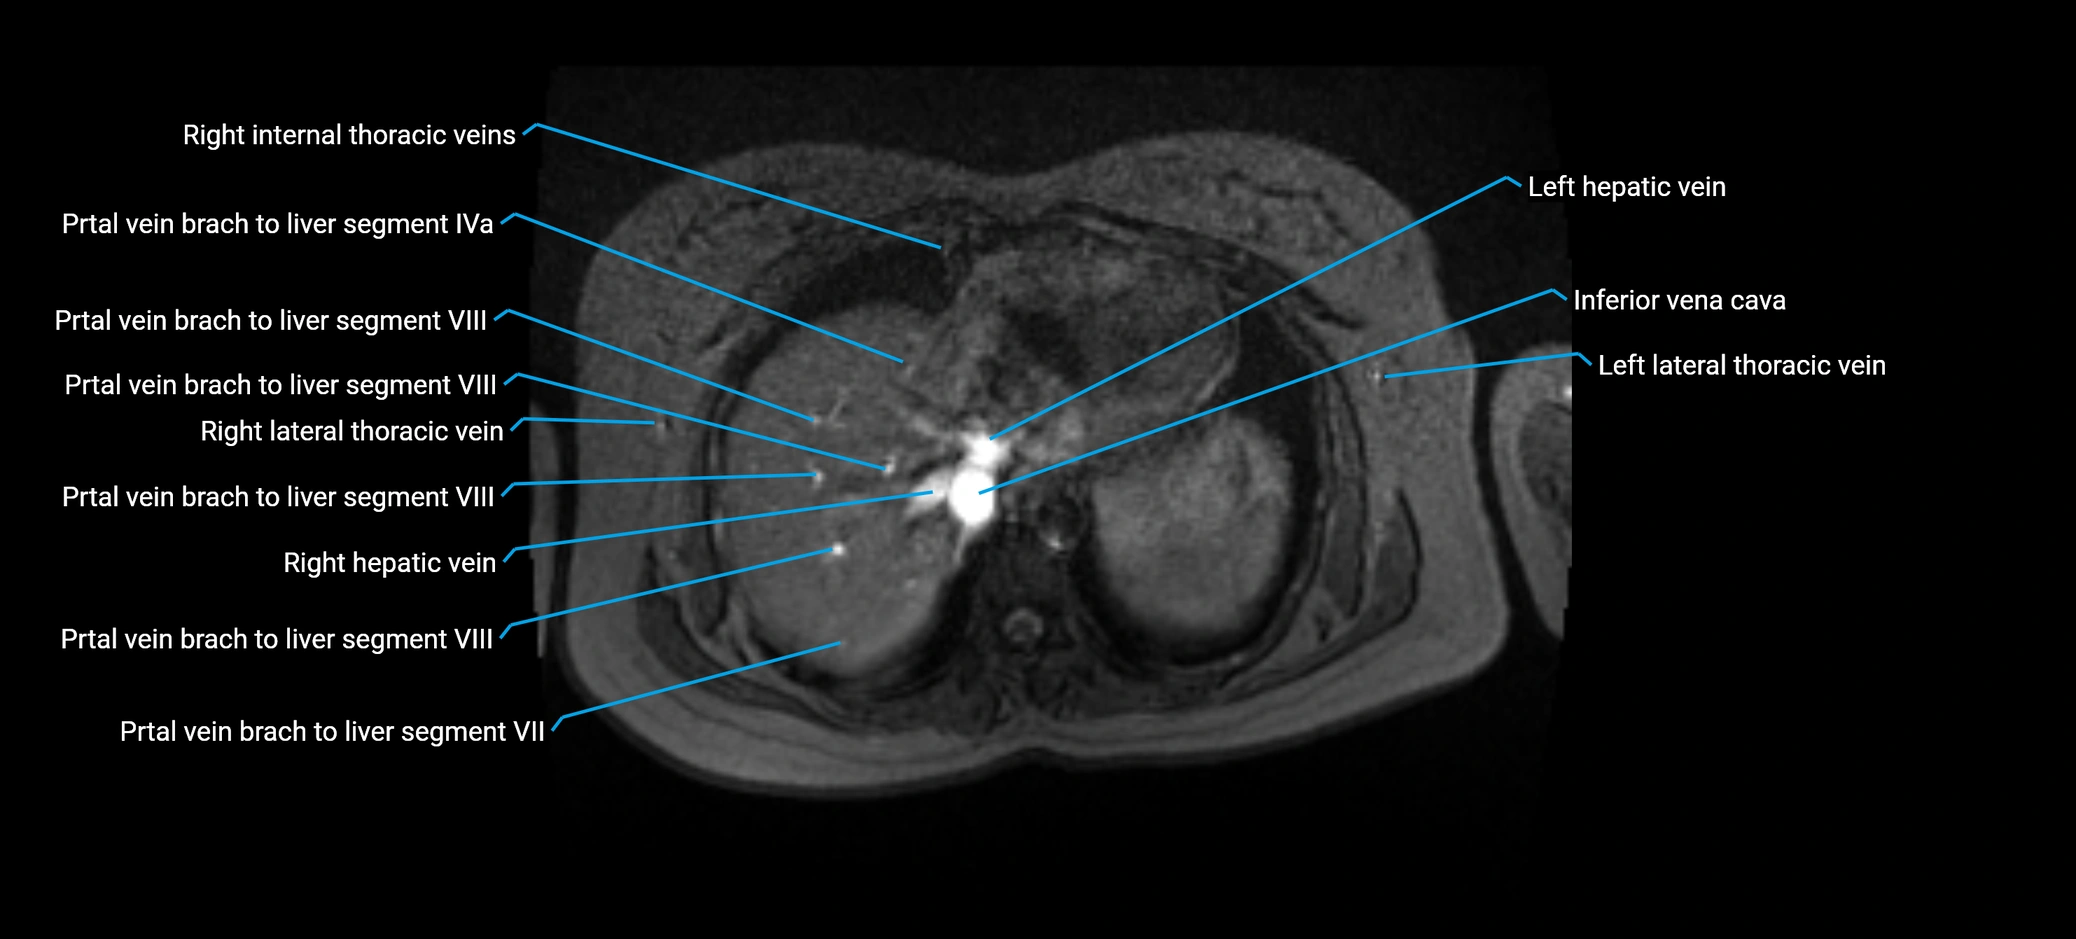

The anterior right branch of the portal vein is a major intrahepatic division of the right portal vein. After the main portal vein bifurcates into right and left branches, the right portal vein divides into anterior and posterior segmental branches.

The anterior right branch supplies the anterolateral liver segments (Segment V) and anteromedial liver segments (Segment VIII) within the right hepatic lobe. It operates as a key vascular route delivering nutrient-rich portal venous blood to the central and superior right liver.

This segmental vasculature is of major importance in hepatic surgery, embolization, segmental resection, transplantation, and imaging-based liver segmentation.

MRV TOF (Time-of-Flight MR Venography):

• Appears as a bright, high-signal vascular channel representing flowing blood

• Clearly shows branching pattern of right portal vein into anterior and posterior branches

• Best in coronal or axial reconstructions for segmental mapping

• No need for contrast, relies on flow-related enhancement

Post-Contrast T1 Fat-Sat GRE:

• Enhances brightly and homogeneously during the portal venous phase

• Clearly delineates branching into segments V and VIII

• Best sequence for evaluating patency, caliber, and anatomic variants

• Early arterial phase: minimal enhancement

• Delayed phase: gradual washout but still brighter than hepatic parenchyma

MRI image

image